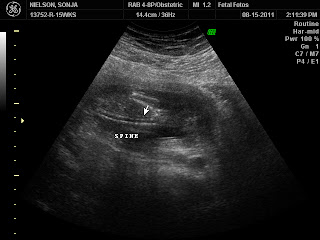

I just wanted to post these pictures mostly for us to remember our baby. We were so excited to have another chance at being parents so soon after suffering a miscarriage at 7 weeks. The D&C was 4/29/2011, a Friday, and 16 weeks later (to the day) we learned our new son, who was so eager to come to our family (16 weeks gestation) no longer had a heartbeat and I would need to be scheduled for induction soon. I'm so happy I felt inspired to get this ultrasound done Monday. We were able to see all of our baby and his beautiful heartbeat. I feel so blessed for this tender mercy and inspiration! I know this day and the following will be hard but I know our Savior loves me and our family and we will be a complete family some day. Thanks to my wonderful friends and family for your support. I love you so much!